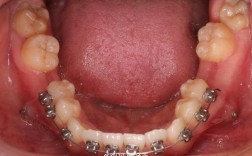

(图片来源网络,侵删)- 南京医科大学附属口腔医院(江苏省口腔医院): 这是南京乃至华东地区口腔医疗的标杆,综合实力最强,尤其在正畸领域拥有众多资深专家和教授。优势: 技术顶尖、设备先进、处理复杂疑难病例能力强、学术氛围浓厚、价格相对透明(但整体费用可能较高)。劣势: 人流量极大,预约排队时间长(尤其是知名专家号)、环境和服务体验可能不如私立、复诊时间可能较难安排。

(图片来源网络,侵删)- 执业许可: 查看是否持有有效的《医疗机构执业许可证》。

(图片来源网络,侵删)- 你的牙齿问题复杂程度?(是简单排齐还是需要拔牙、手术?)